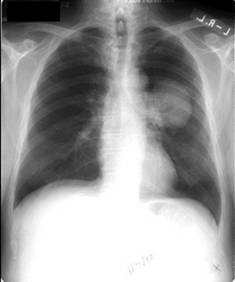

Рентгенологическое исследование является одним

из основных методов диагностики опухолей лёгкого и позволяет своевременно

обнаружить его у 80 % больных. В качестве скринингового метода используется

флюорография, которая обычно проводится во время профилактических медосмотров.

При выявлении изменений (солитарный лёгочный узел, ателектаз и т.д.) на

флюорограмме или при наличии клинических показаний применяют рентгенографию в

двух проекциях и компьютерную томографию. Кроме того, компьютерная томография

является наиболее информативным методом диагностики метастазов в других

органах.